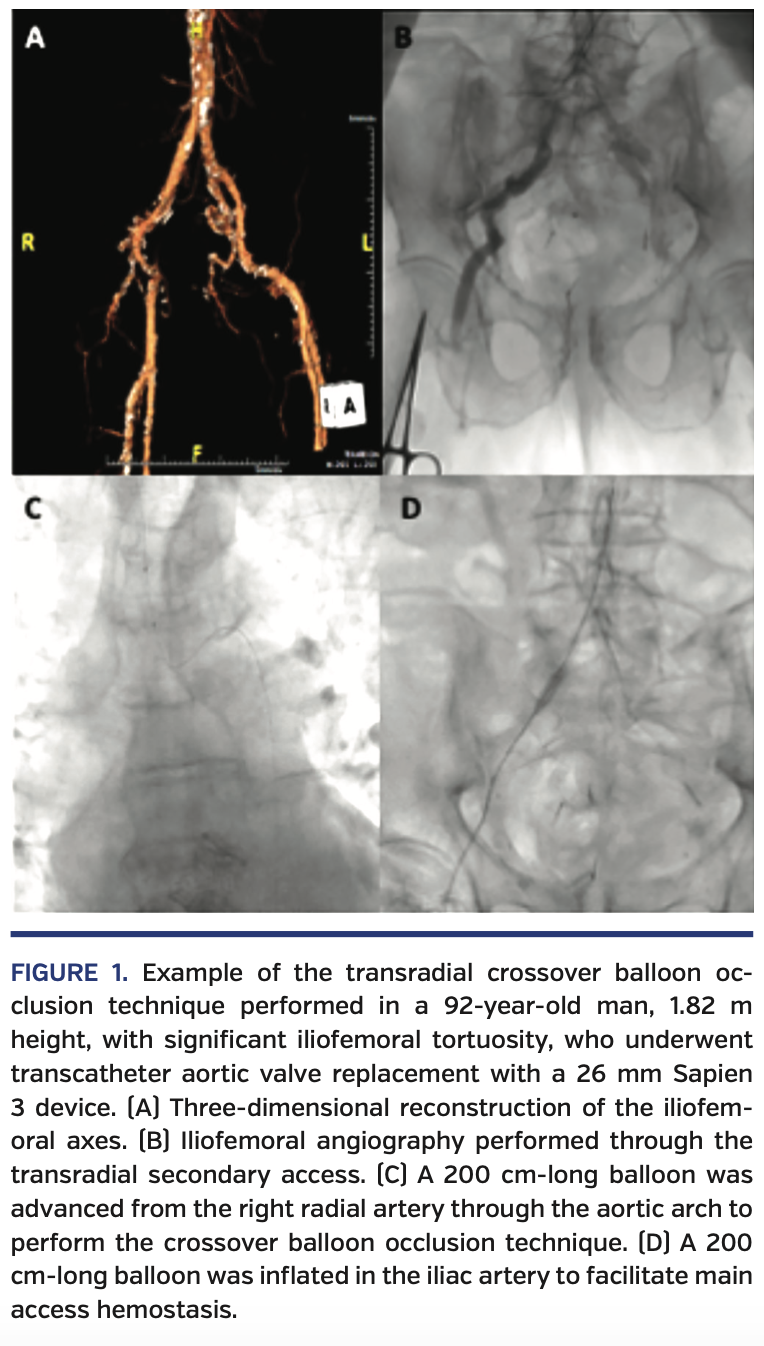

Transradial Crossover Balloon Occlusion Technique for Primary Access Occlusion Valve When the button is pressed gas flow. Multidetector computed tomography (ct) is an important tool for assessing the risk of coronary occlusion in native valve tavr. The purpose of the valve is to restrict the exhaust side of. 8,13 although the optimal methodology for ct screening of the risk of coronary occlusion in the context of viv is still in. Occlusion Valve.

Transradial Crossover Balloon Occlusion Technique for Primary Access Occlusion Valve The purpose of the valve is to restrict the exhaust side of. When the button is pressed gas flow. Multidetector computed tomography (ct) is an important tool for assessing the risk of coronary occlusion in native valve tavr. In as few as 30 seconds, the pressure that builds up. 8,13 although the optimal methodology for ct screening of the risk. Occlusion Valve.